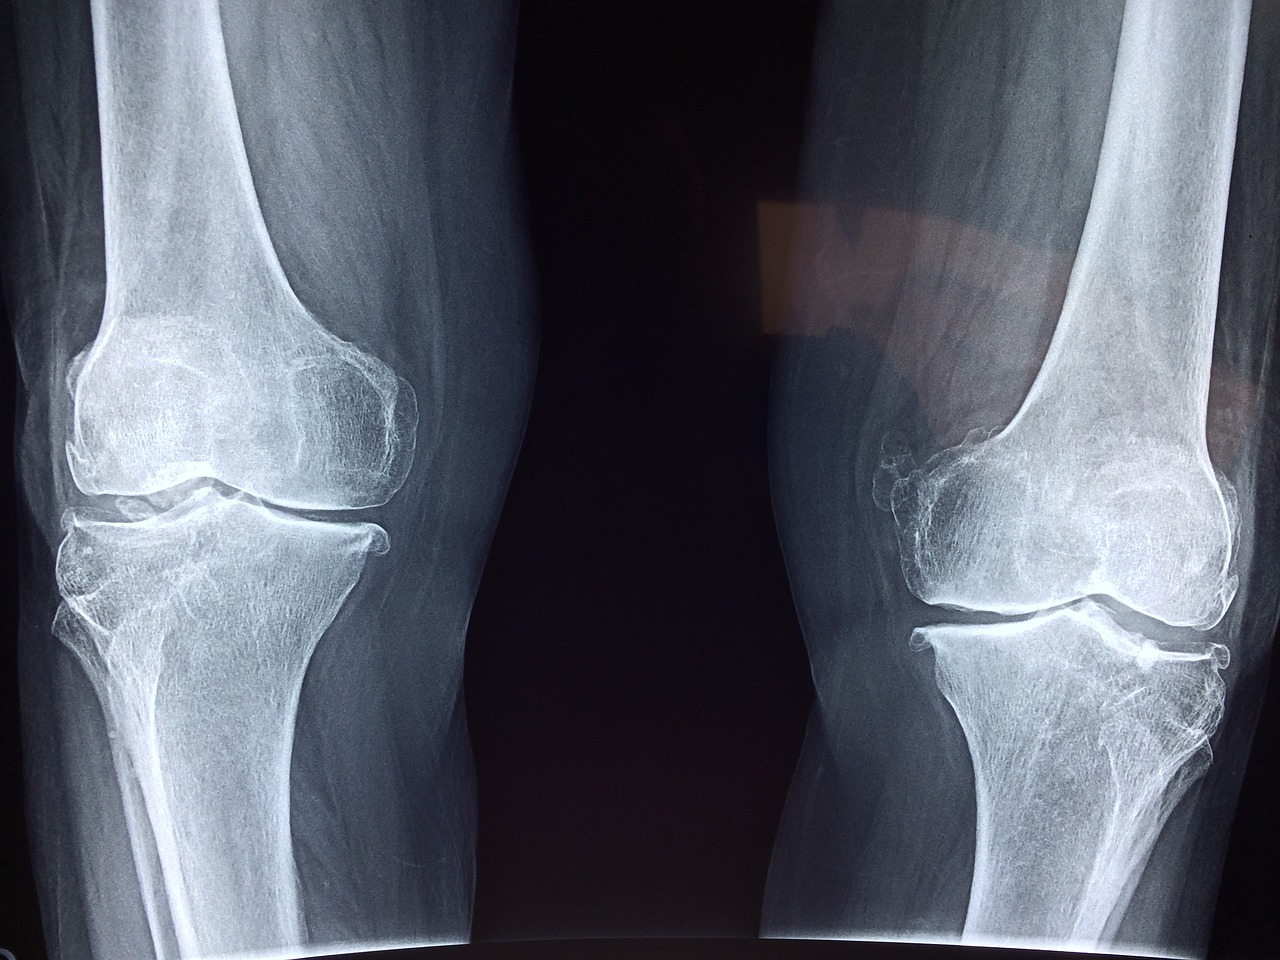

However, as time goes on, these cancer cells can spread to nearby organs and even reach the bones (secondary stage). When cancer cells move from their original site to the bones, it’s called bone spread or skeletal metastasis. This can cause the bone to be in pain, or even get fractured. In this article, we’re going to learn more about the types and symptoms of bone spread or skeletal metastasis.

- Bone that breaks easily, even at the slightest injury

- Swollen areas around the bone that have been contaminated with cancerous cells